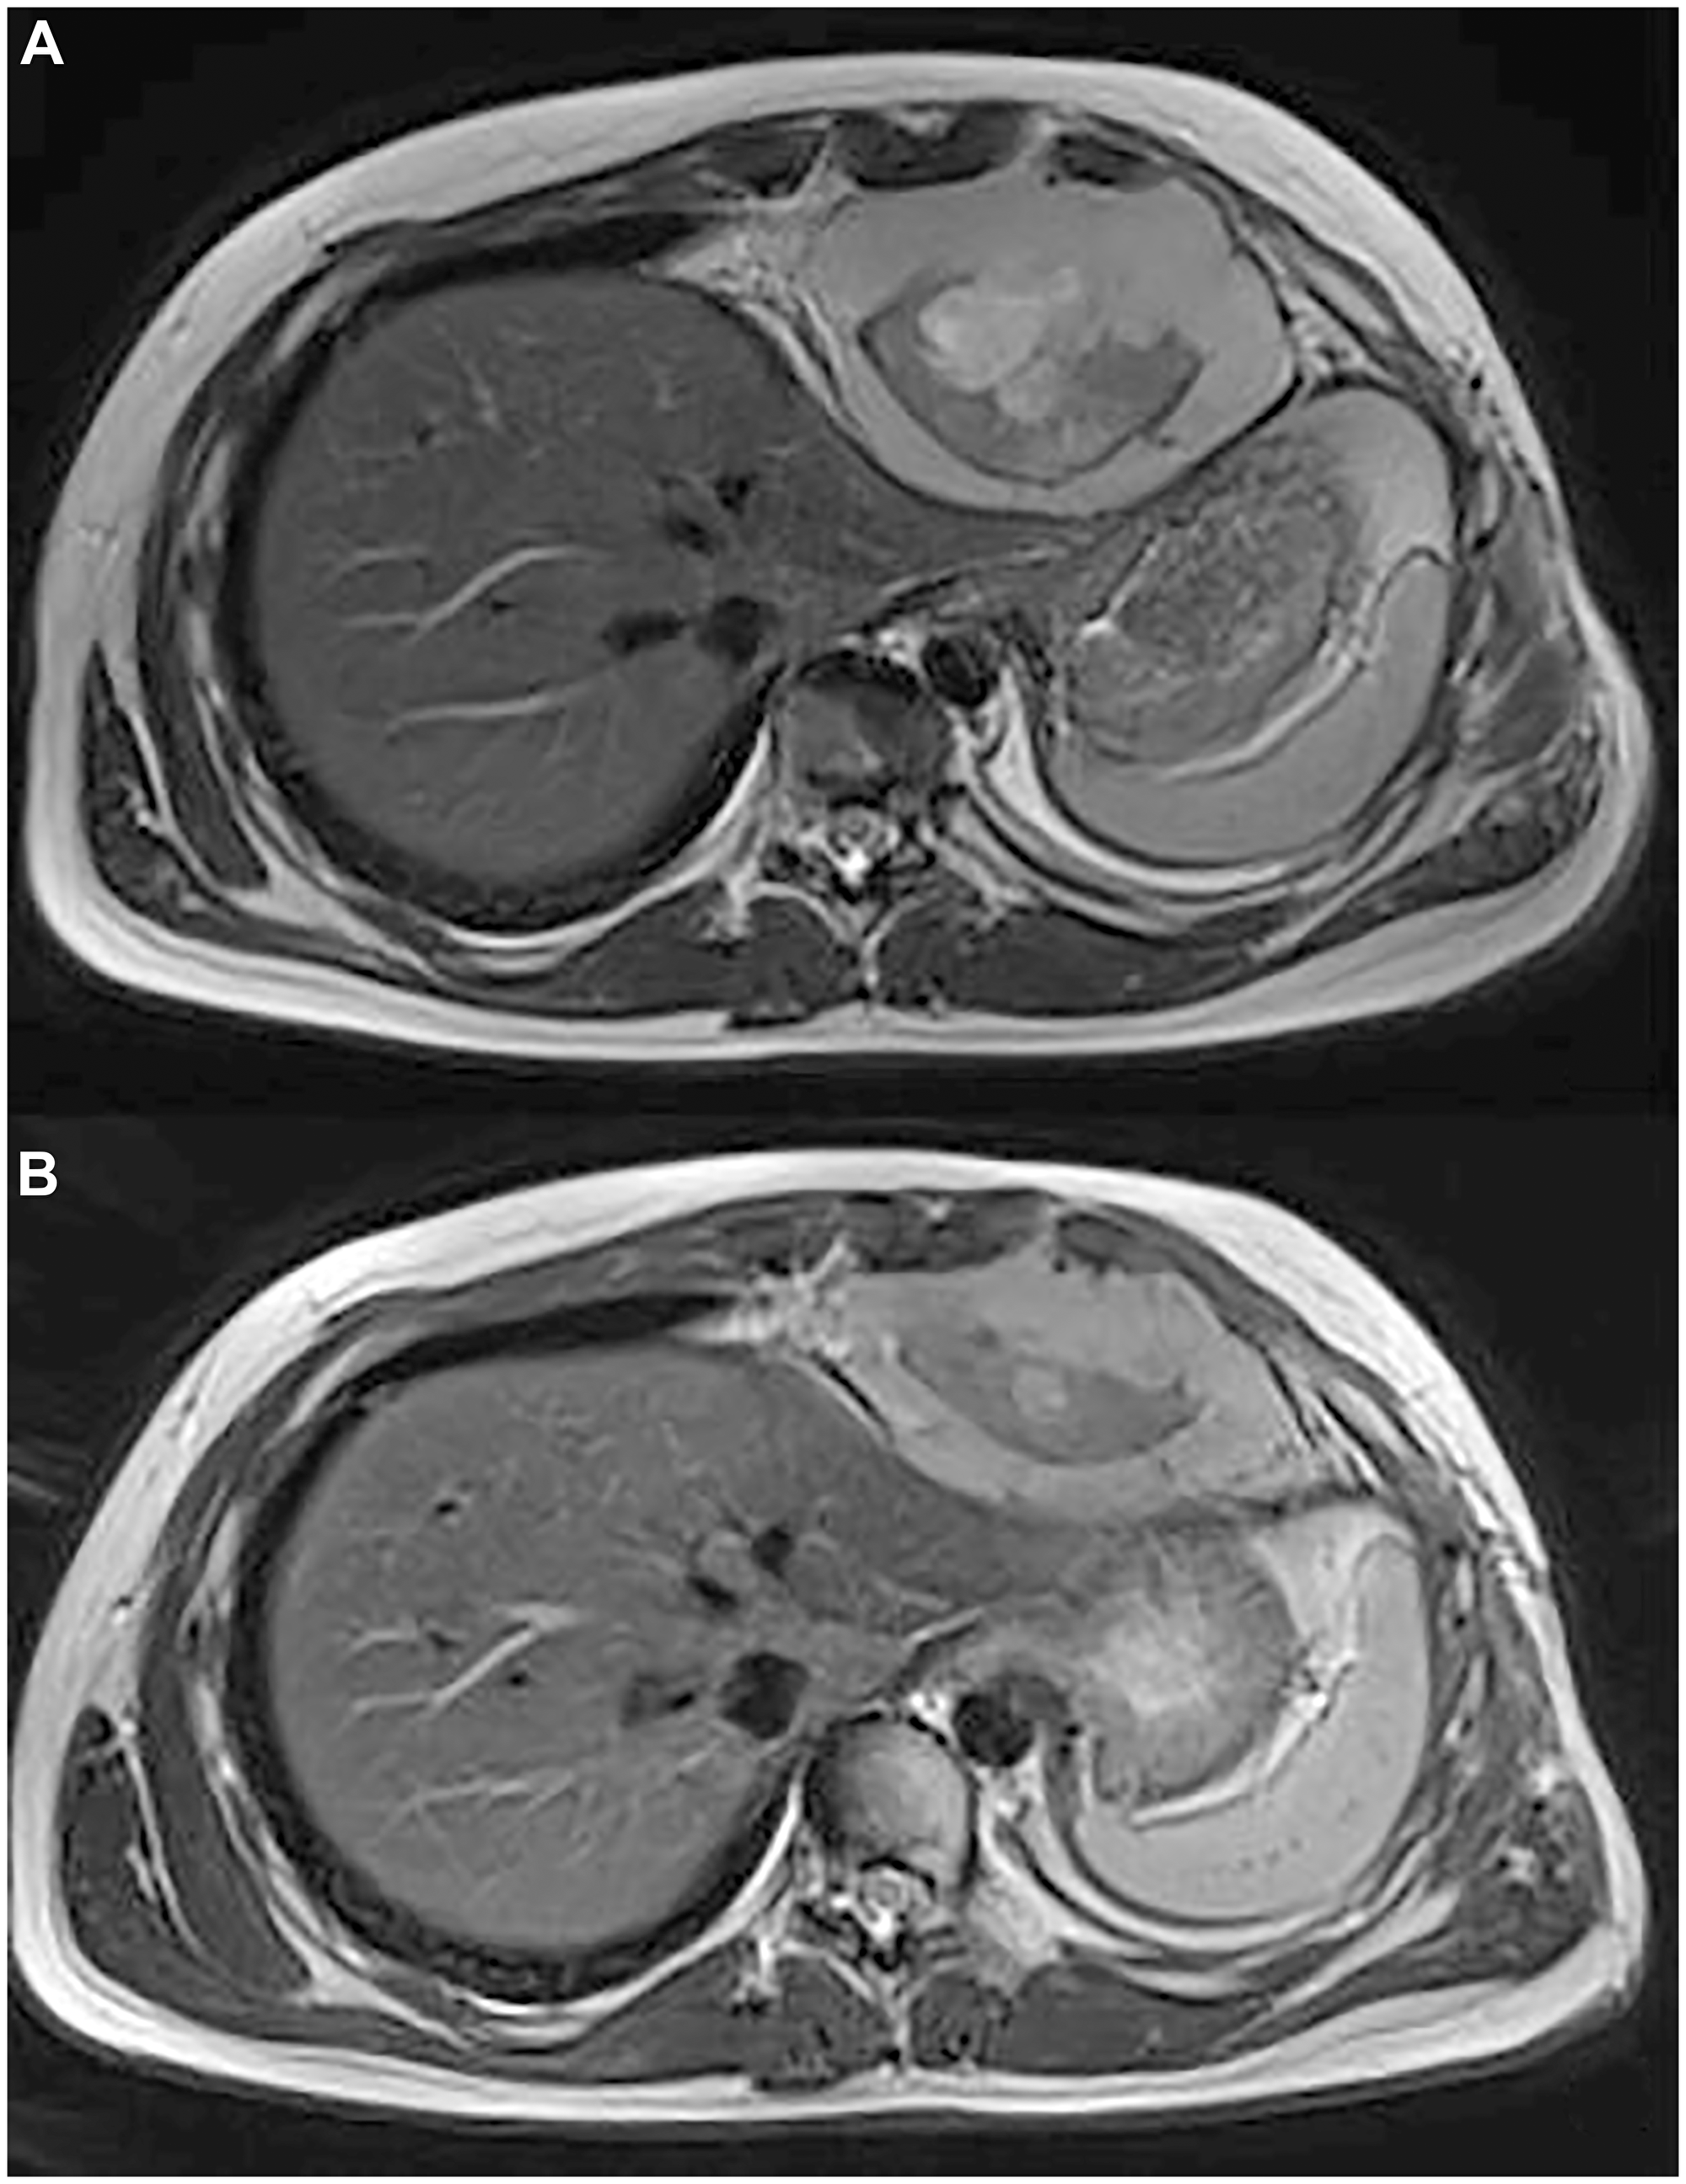

(A) Axial T2 MR shows a heterogeneous mass in the cardiophrenic space with evidence of anterior chest wall invasion and intercostal invasion. (B) Axial T2 MR shows 35 % of reduction in size of the mass in the cardiophrenic space.

Figure 2: (A) Axial T2 MR shows a heterogeneous mass in the cardiophrenic space with evidence of anterior chest wall invasion and intercostal invasion. (B) Axial T2 MR shows 35 % of reduction in size of the mass in the cardiophrenic space.

A 15-year-old boy was diagnosed has having intrathoracic SS, diagnosis was confirmed by SS18::SSX1 fusion transcript detected by reverse-transcriptase polymerase chain reaction (Figure 1A). Staging work-up of the disease did not show any distant metastases. The patient received chemotherapy with 3 cycles of doxorubicin and ifosfamide, 1 cycle of ifosfamide, which resulted in partial response. The patient underwent tumour resection with left upper lung lobe, parietal and pericardial pleura. Subsequently he received adjuvant chemotherapy, with 1 cycle of ifosfamide, and consolidation local radiotherapy (RT) with Volumetric Modulated Arc Therapy technique (VMAT), total dose of 50.4 Gy in daily fractions of 1.8 Gy. One month after RT, a local relapse was found on magnetic resonance image (MRI) without distant lesions. Based on the strength of reported efficacy in phase III trial [10], patient was therefore treated with multitargeted tyrosine kinase inhibitor Pazopanib monotherapy at dose of 800 mg QD, discontinued 72 hours later for acute myopericarditis possible related to RT late effects. After resolution of the cardiotoxicity, a third-line nucleoside metabolic inhibitor Gemcitabine (750 mg/mq/dose) every two weeks was started, as an alternative treatment which may be considered in patients affected by SS who cannot tolerate or are resistant to standard chemotherapy [11]. We chose to omit docetaxel considering previous toxicities. After 4 courses of Gemcitabine, a new MRI showed intrathoracic tumour progression and a new lesion appearance at the homolateral thoracic wall. Patient was referred to our internal molecular tumour board (MTB). In order to identify molecular target for cancer, the TruSight Oncology 500 panel targeting 523 cancer-relevant genes on tumour resection has been performed. Next generation sequencing (NGS) analysis showed low tumour mutational burden (TMB) and stable microsatellite instability (MSI) status and detected a BRAF p.V600E (c.1799T>A) mutation with a variant allele frequency (VAF) of 49% in a sample with histologically estimated tumour cell ratio of 85% (Figure 1B). The mutation BRAF p.V600E was also investigated and confirmed in PCR on the post-therapy tumour biopsy. Vemurafenib, at initial dose of 240 mg BID was started in low dose regimen taking into consideration the toxicity profile of the drug and the previous cardiological and pulmonary patient’s morbidities. Despite starting low dosage of the drug, radiological examination after 4 months unexpectedly showed partial response (PR) for both intrathoracic and chest wall lesions, according to RECIST version 1.1 [12], with volume shrinkage of the intrathoracic lesion of 35% (Figure 2A, 2B). The dosage at 480 mg BID was increased and well tolerated. Patient experienced only G1 folliculitis, G2 cough, G1 asthenia, G1 hyperuricemia. Toxicity was graded according to the National Cancer Institute’s Common Toxicity Criteria, version 5.0 [13]. Patient is currently alive with a progression free survival (PFS) of 6 months and an overall survival (OS) of 19 months.